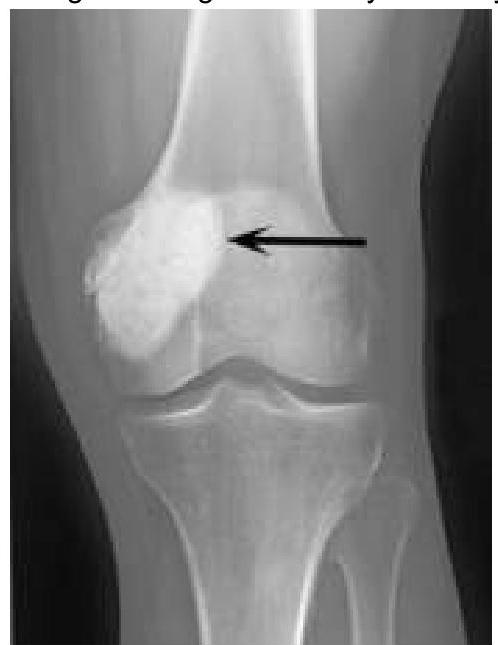

Explanation: ***Paget's disease*** [1] - Characterized by abnormal **bone remodeling**, leading to an increase in bone size and deformity, particularly in the **maxilla**, causing enlargement [1]. - Associated with complications such as **loss of visual acuity** (due to involvement of the skull) and **deafness** from auditory canal changes [1][2], making this the most fitting diagnosis. *Fibrous dysplasia* - Typically presents with **fibrous replacement** of bone, not specifically causing deafness or visual acuity loss. - Customarily involves the **classic "ground glass" appearance** on imaging, not the structural enlargement seen in Paget's disease. *Osteogenesis imperfecta* - Mainly causes **brittle bones** and frequent fractures, not associated with **maxillary enlargement** or changes in auditory function. - Rarely causes visual acuity loss, which is not a feature of this condition. *Osteomalacia* - Primarily characterized by **softening of bones** due to vitamin D deficiency, leading to weakness rather than structural changes like maxillary enlargement. - Symptoms like **bone pain** or **muscle weakness** occur, but not specifically loss of auditory function or visual acuity. **References:** [1] Kumar V, Abbas AK, et al.. Robbins and Cotran Pathologic Basis of Disease. 9th ed. Bones, Joints, and Soft Tissue Tumors, pp. 1192-1194. [2] Cross SS. Underwood's Pathology: A Clinical Approach. 6th ed. Common Clinical Problems From Osteoarticular And Connective Tissue Disease, pp. 669-670.